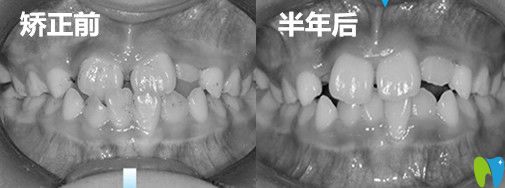

兒童反頜矯正半年后牙齒變化圖:

之后我們差不多一個(gè)星期復(fù)查一次,大概半年左右,兒子的矯正終于結(jié)束了,反頜解除啦,心里非常高興。

兒子地包天矯正前后效 果對(duì)比圖:

從對(duì)比圖中,不難看出孩子的牙齒已經(jīng)有了很大的變化,嘴型也發(fā)生了很大變化,之前閉嘴的時(shí)候,下巴稍微有點(diǎn)前突,現(xiàn)在輪廓也得到了不錯(cuò)的改善!